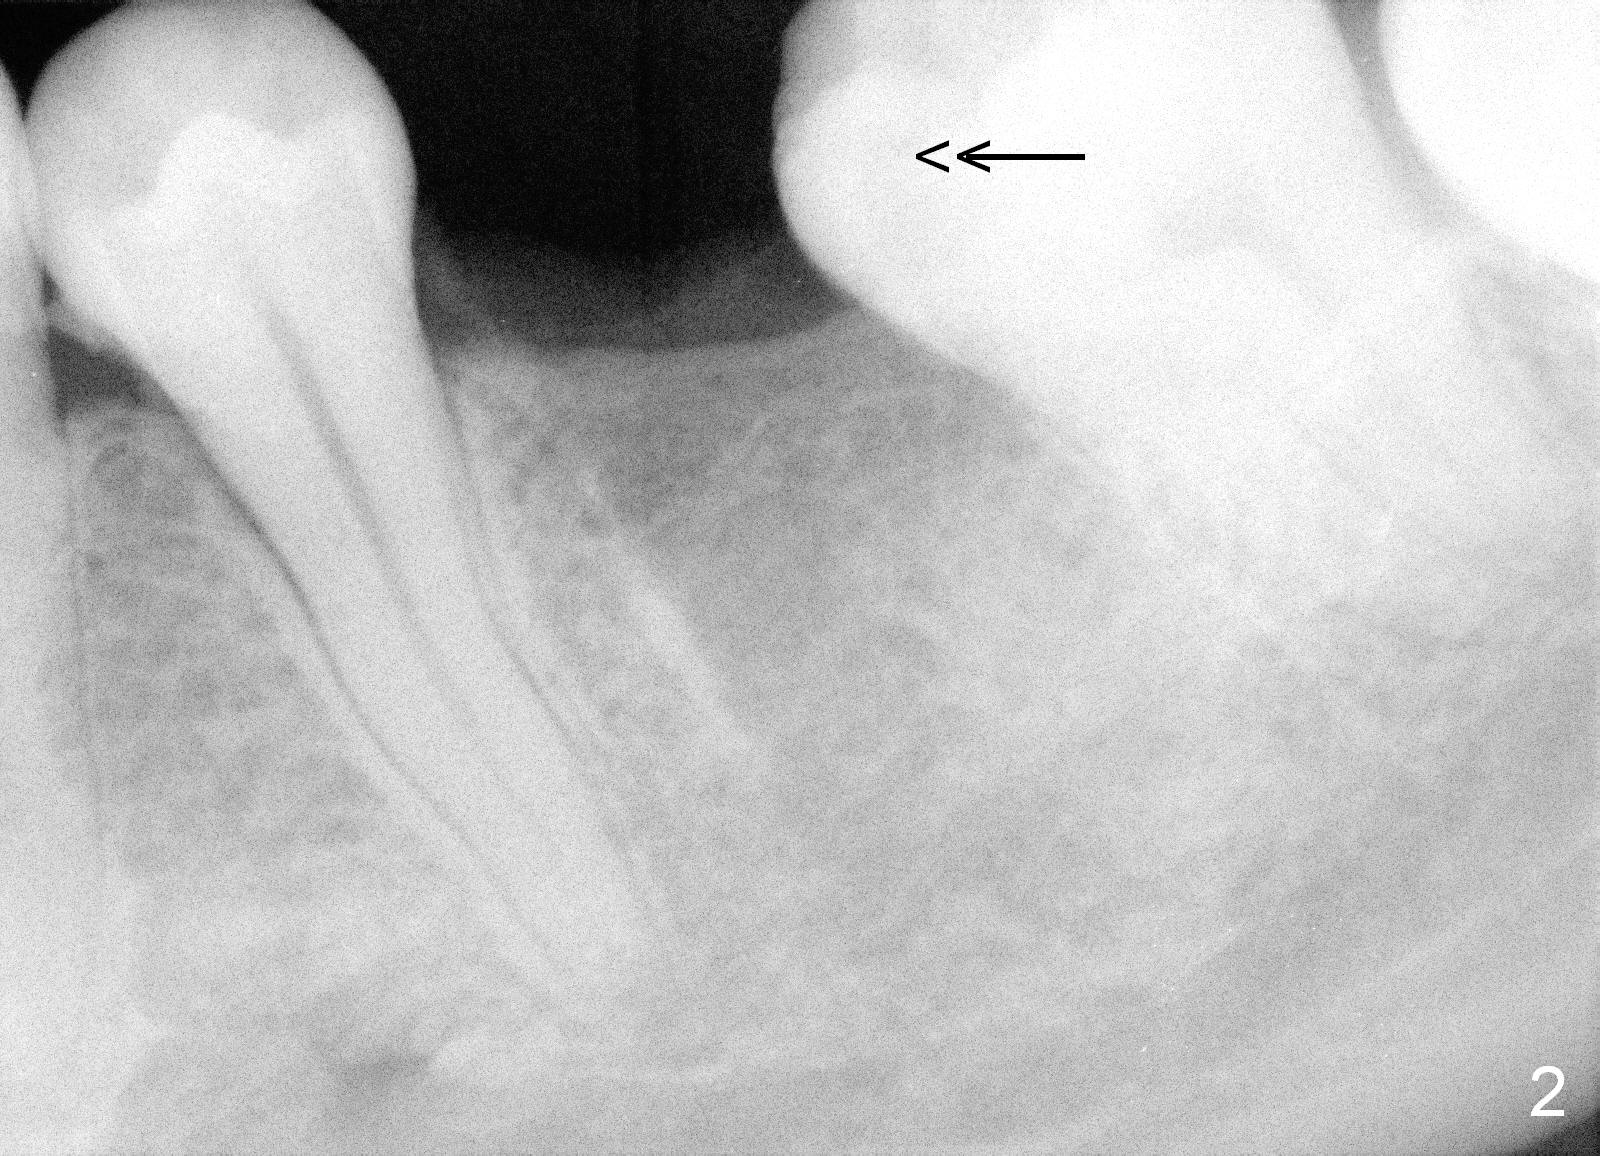

A 29-year-old man presented for #19 extraction a year ago (Fig.1). Probably due to long-termed loss of the distal portion of the crown of #19 (*), the tooth #18 has undergone mesial tilting (arrow). Now he returns requesting implant, but the tilting is worse (Fig.2 double arrows). What X-ray cannot show is severe atrophy buccolingually, increasing difficulty in implant placement. A much smaller implant can be placed (Fig.3), as compared to an immediate implant.